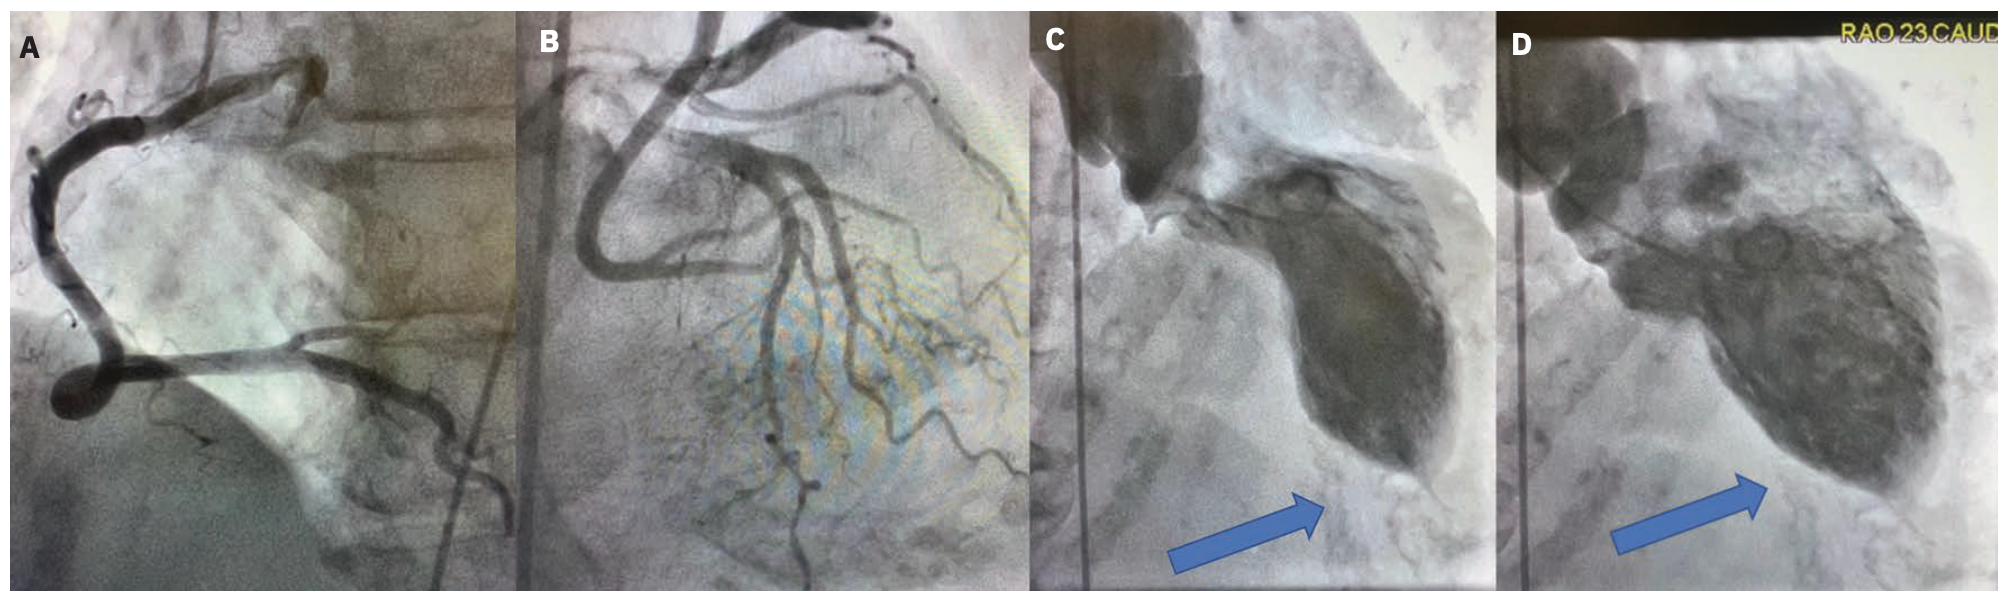

Figure 2 illustrates two cases of SCAD diagnosed in women with ST-elevation MI symptoms. In the first case, the patient was treated with medical therapy because the dissection was located too distal in the left anterior descending coronary artery to deploy a stent. The second patient was treated with a drug-eluting stent. Both patients had successful outcomes, and are also being managed with medications and regular cardiology follow-up care.